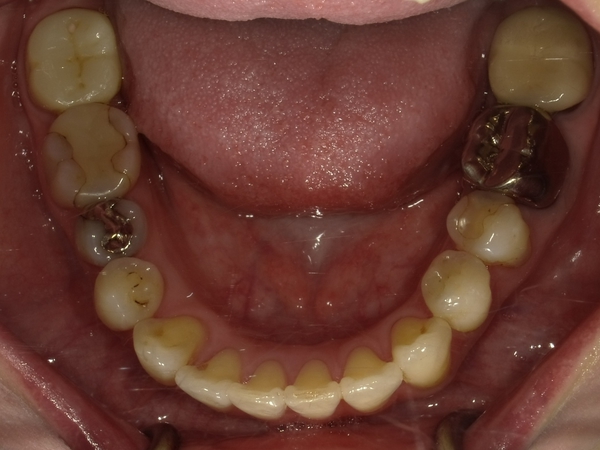

Before After

●ご相談内容:前歯が曲がっている●矯正の種類:マウスピース型「矯正インビザラインGO」●治療期間:18週●治療費用:66万円(税込)